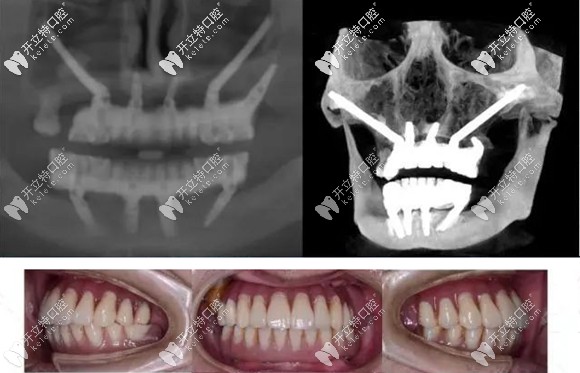

簡單來說,把種植體植入到顴骨和翼板骨上的種植方法,就叫做穿顴穿翼種植技術(shù)。

對于上頜骨切除、上頜骨重度萎縮,做常規(guī)的上頜竇內(nèi)外提升,也沒有辦法達(dá)到種植條件的無牙頜患者,就需要向頜面部的顴骨和翼板找可植入種植體的骨頭。

而這部分的骨頭也適合作為種植位點(diǎn),它不會(huì)像牙槽骨那樣萎縮吸收。但是,也由于這個(gè)位置比較靠上,所以,手術(shù)的難度也就大大增加了,一般的口腔機(jī)構(gòu)都無法進(jìn)行這項(xiàng)手術(shù)。

穿顴穿翼就是種植體植入到顴骨和翼板骨上的種植方法